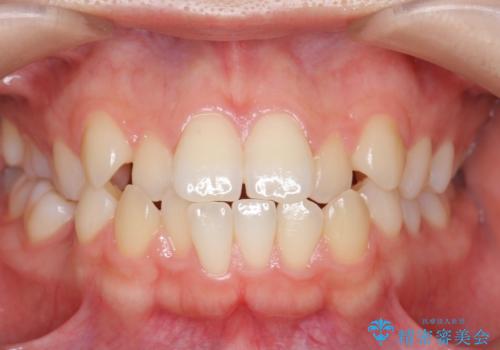

かみ合わせが悪いところを ワイヤー矯正でしっかり治療 マウスピース矯正は難しい症例

- 歯並びが気になるとのことで来院。

前歯、奥歯ともに反対咬合になっており、また上顎の前歯が少し突出気味でした。

上下左右の小臼歯を抜歯しています。

時間はかかりましたがしっかりかみ合わせから治すことができました。